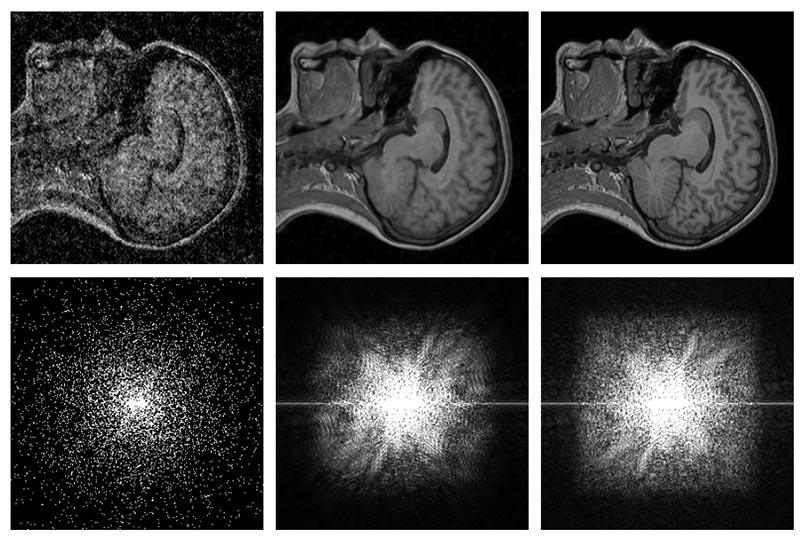

Chương trình có tên gọi Noise2Noise AI được “huấn luyện” bằng cách thêm ngẫu nhiên độ noise vào 50.000 bức ảnh. Sau một thời gian “học tập”, AI có thể loại bỏ hầu hết những thành phần bị noise, nhiễu hạt và thậm chí là con dấu, đưa ảnh trở nên rõ ràng gần như giống với ảnh nguồn.

Điều đặc biệt hơn là AI hoàn thành công việc mà không cần bất cứ ví dụ nào về ảnh “sạch”. Tất cả những gì nó cần là những trường hợp hình ảnh bị hỏng.

Được biết, nghiên cứu mới này ngoài 'dọn dẹp' noise trên ảnh chụp bằng điện thoại hoặc máy ảnh trong điều kiện ánh sáng yếu còn có tác dụng cải thiện hình ảnh thiên văn và phép scan MRI.